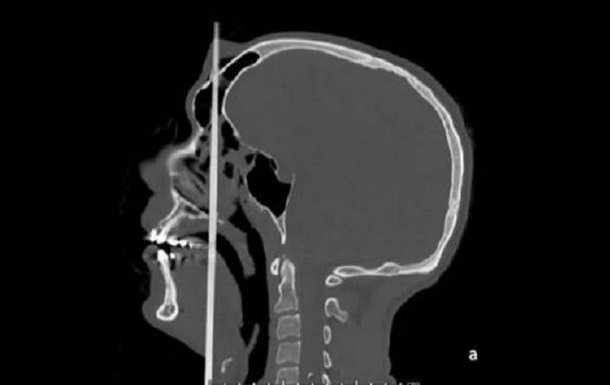

Стрела вошла в голову человека в районе подбородка, в том месте, где начинается язык. Она прошла насквозь через весть череп и вышла посреди лба.

Хирургам удалось разрезать стрелу и извлечь ее из головы пациента. После операции мужчину на двое суток поместили в реанимацию, потом перевели в в ЛОР-отделение, а после - в отделении психиатрии.